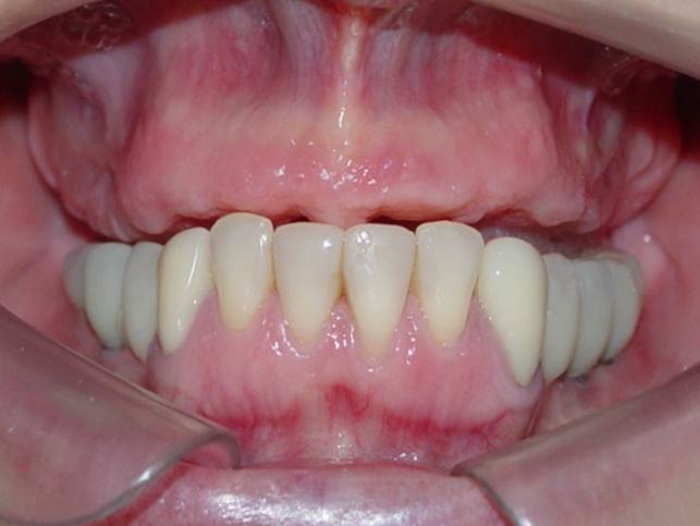

Sorriso final do caso terminado em março de 2012